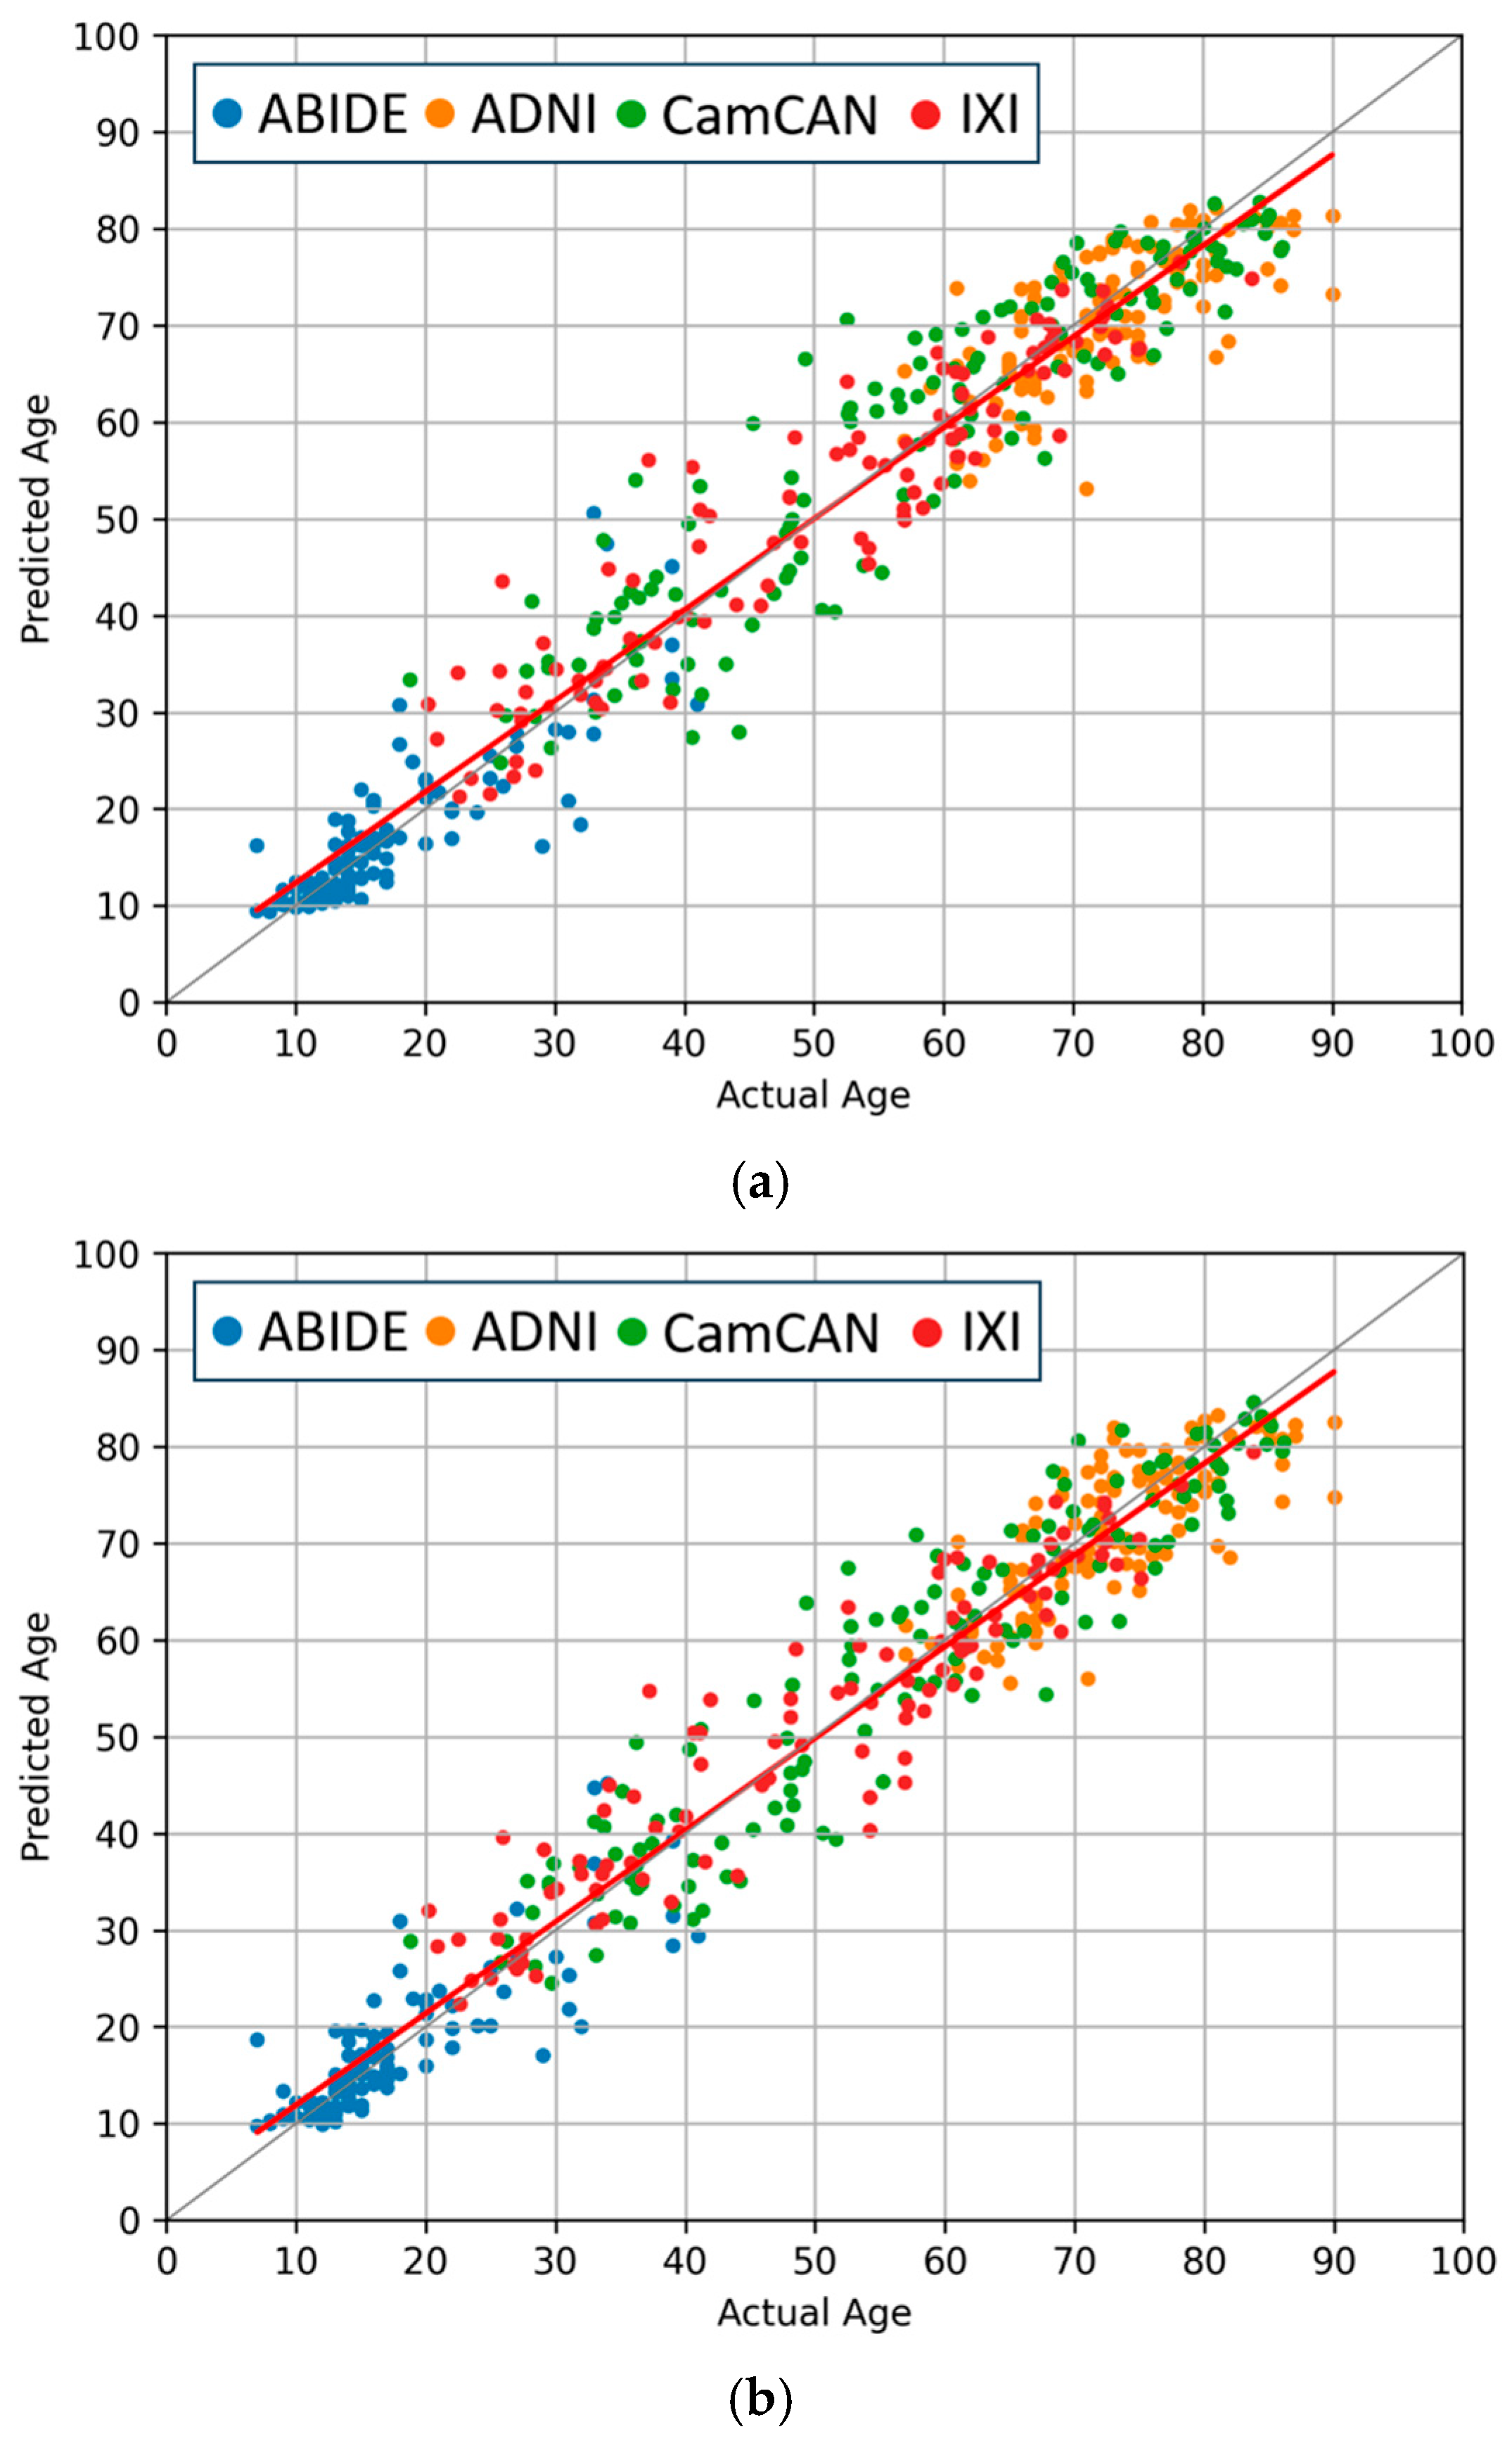

4.3. Comparisons of Regression and Softmax Performance

4.4. Evaluation of Data Augmentation